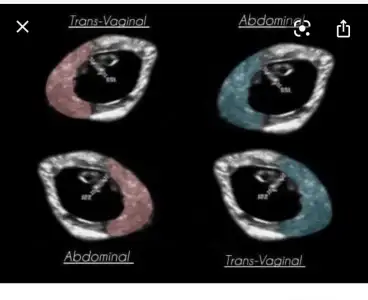

Ay bilemedim ki anlayamadım su görsele gore anlayabilen var mi

Eklentiler

• 8F825B05-CF42-42AD-8E52-72D300886CFC.webp

8F825B05-CF42-42AD-8E52-72D300886CFC.webp

18,7 KB · Görüntüleme: 67